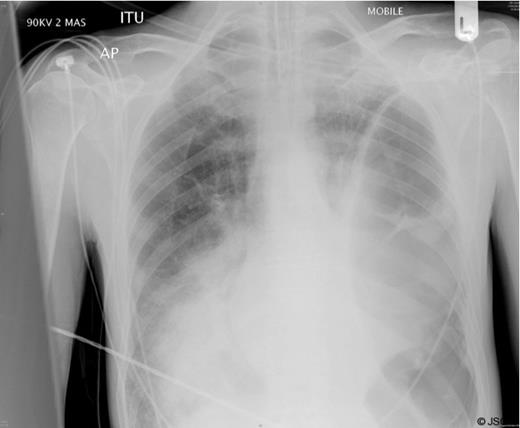

A clinical diagnosis of a possible spontaneous rupture of the diaphragm was made. The patient underwent an emergency laparotomy as he was not stable enough to undergo cross-sectional imaging to confirm the diagnosis. There were no abnormal findings at laparotomy. A left sided chest drain was immediately inserted with release of air under tension and pus (Figure 2).

The patient remained intubated for five days, initially being weaned onto CPAP, and spent ten days in total on the intensive care unit. He developed a small residual empyema on the left side after the chest drain was removed which resolved with an extended course of antibiotics. He spent a total of 6 weeks in hospital before discharge with support at home. At a follow up outpatient appointment two months he remained well.